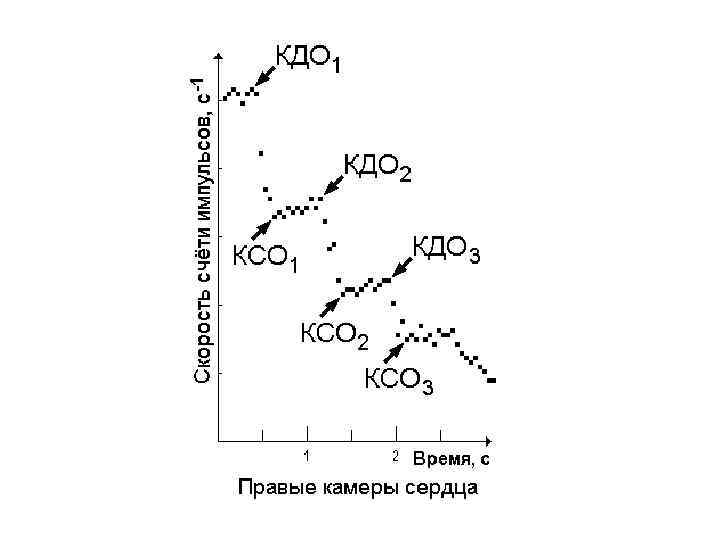

Регистрация первого прохождения РФП

Регистрация первого прохождения РФП

Вычисление фракций выброса ЛЖ и ПЖ

Вычисление фракций выброса ЛЖ и ПЖ